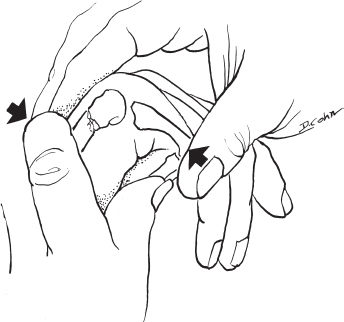

- If apex-dorsal angulation is greater than acceptable, attempt closed reduction using Jahss maneuver.

- Do not splint in the Jahss position because of risk of PIP flexion contracture and skin necrosis.

Posteroanterior, lateral, and oblique radiographs revealed a fifth metacarpal neck fracture with 60 degrees apex dorsal angulation and volar comminution (Fig. 41–1). No other abnormalities were noted.